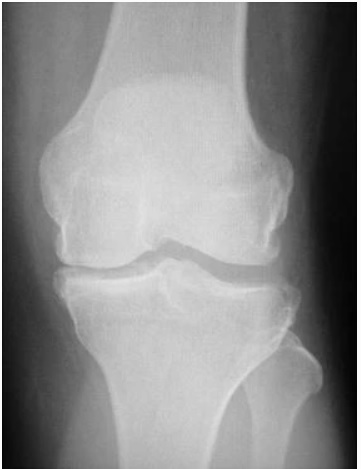

Figure 1. End stage medial compartment osteoarthritis (MOA). Used under CC Attribution 4.0 International License. Source: Mancuso F, Dodd CA, Murray DW, et al. Medial unicompartmental knee arthroplasty in the ACL-deficient knee. J Orthop Traumatol. 2016 Sep;17(3):267–275.